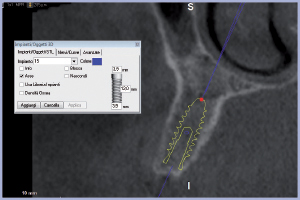

Dopo aver eseguito l’esame, i file dicom vengono acquisiti dal software di programmazione 3Diagnosys LEONE. Studio in modo accurato l’anatomia del mascellare superiore verificando la possibilità di inserimento di impianti nei siti edentuli. Nel quadrante superiore destro progetto in zona 14 e 15 due impianti Exacone® Max Stability 3,75 x 12 mm e nel quadrante superiore sinistro nelle zone 23, 24, 25 e 26 rispettivamente un impianto Exacone® Max Stability 3,75 x 12 mm, un impianto Exacone® 3,3 x 12 mm, un impianto Exacone® Max Stability 3,75 x 10 mm e un impianto Exacone® Max Stability 4,5 x 8 mm (Figg. 1-10).

- Figg. 1-3 – Pianificazione implantare nella “ricostruzione 3D” del software 3Diagnosys Leone

- Figg. 4-9 – Impianti pianificati visti nelle “cross section” su software 3Diagnosys Leone